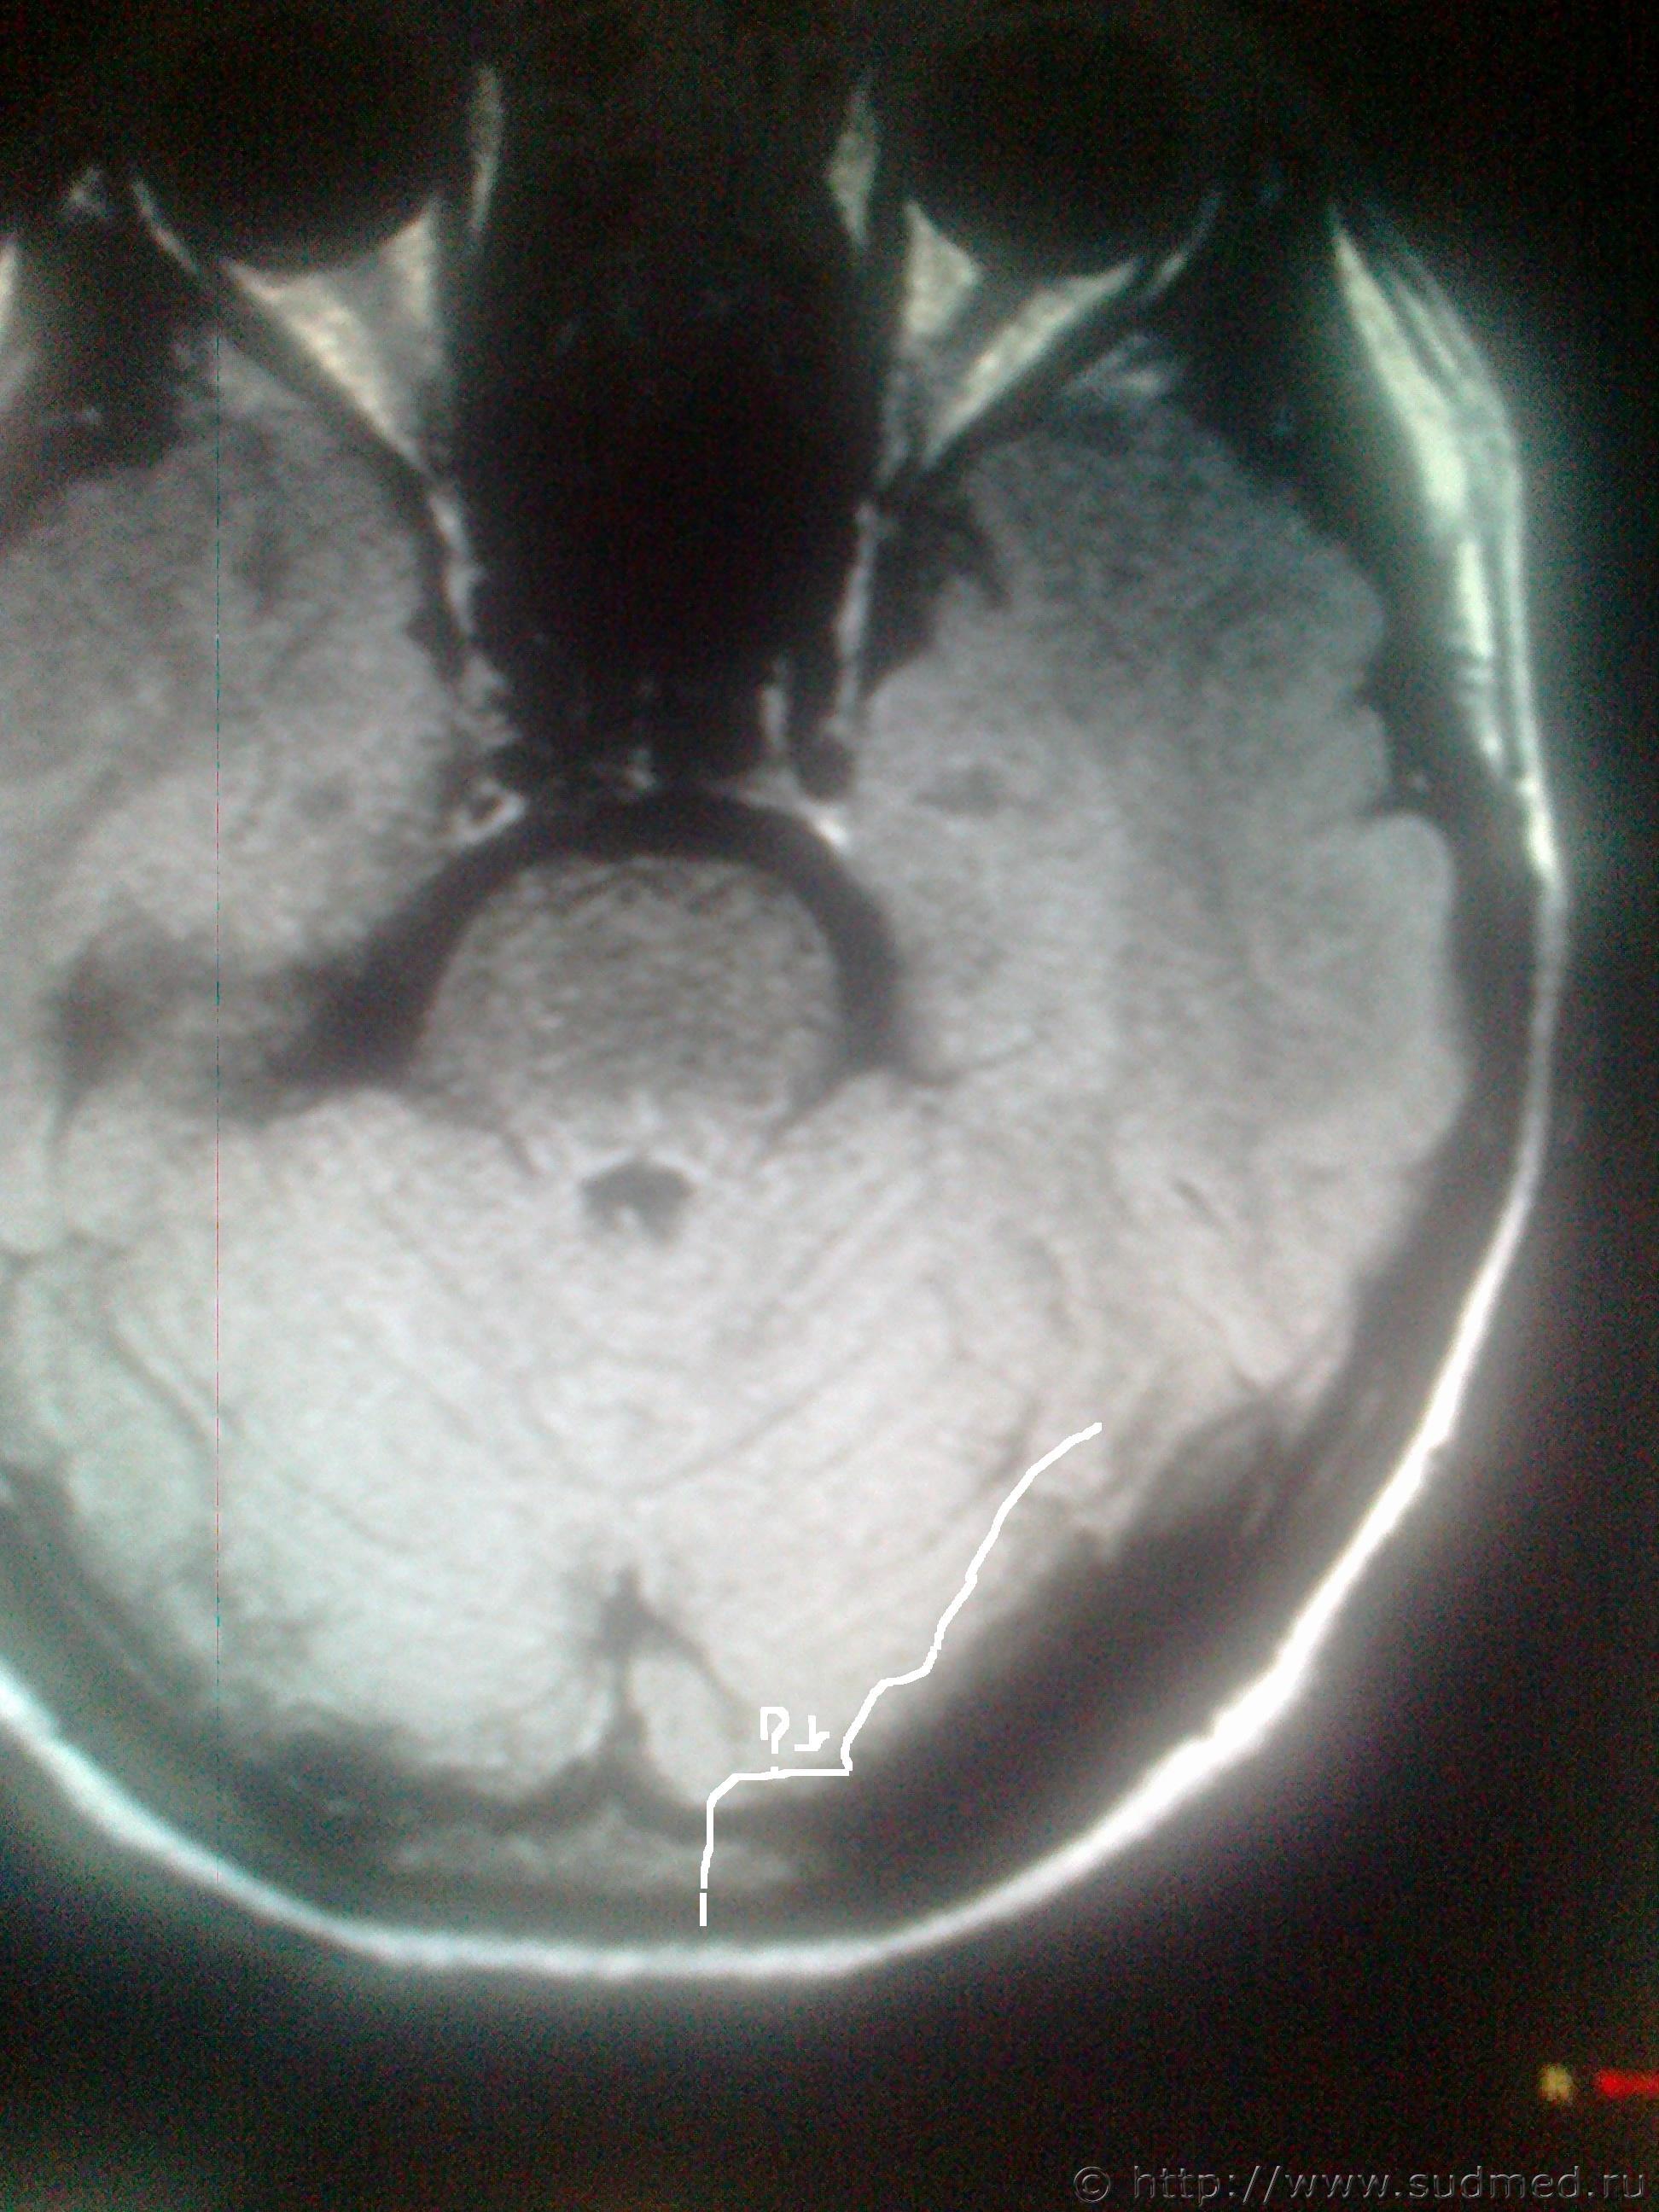

Оч. важно ваше мнение ув. специалисты! В анамнезе травма,на снимках деструкция кости, местно в этой области гиперемия (покраснение). СНИМКИ ПО КОТОРЫМ ВЫСТАВЛЯЮТ ДИАГНОЗ ПРИЛАГАЮ

Эскизы прикрепленных изображений

Судебная медицина - Прикрепленное изображение Судебная медицина - Прикрепленное изображение

Нужны заключение рентгенолога и консультация нейрохирурга.